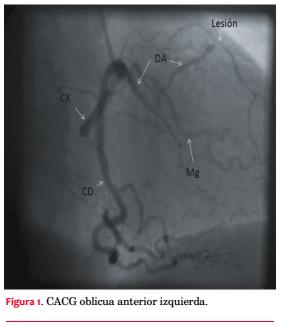

La CACG evidencia una arteria coronaria única, con origen en un ostium en el seno de Valsalva derecho y rápida división de un corto tronco común en arteria coronaria derecha (CD), descendente anterior (DA) y circunfleja (Cx) (figura 1). Tronco sin lesiones. CD dominante, con lesión severa en tercio distal. Descendente posterior con lesión severa ostial y en tercio medio. La DA, de fino calibre, tiene lesión suboclusiva en tercio medio y lesión severa distal. Cx sin lesiones. Gran ramo marginal presenta lesión severa proximal. Se realiza ATC de DA con implante de stent Minivision 2,0 mm por 2,3 mm sin incidentes.